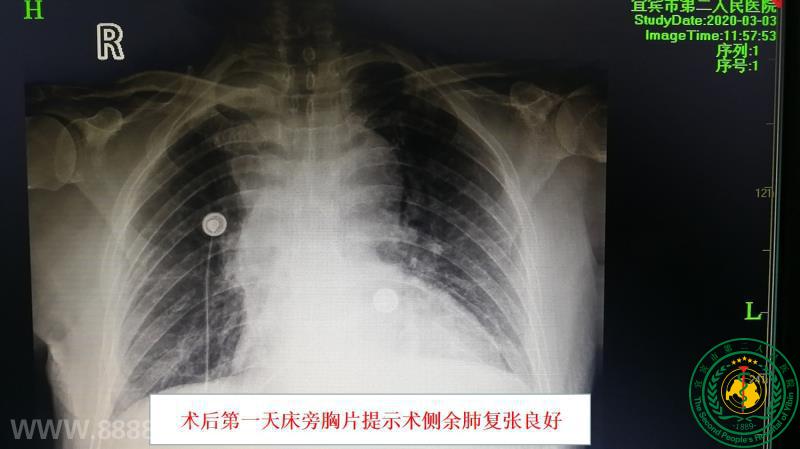

我院率先在川中南独立成功开展胸腔镜袖式肺叶切除半隆突成形术

宜宾市第二人民医院 图文